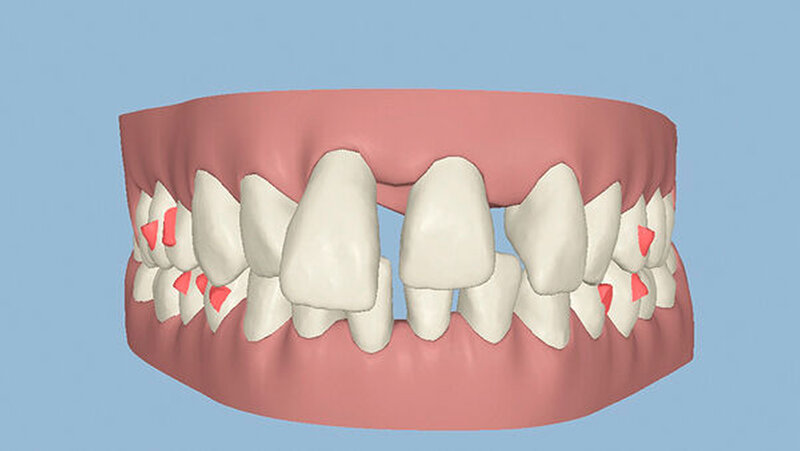

Die Sulkustiefen konnten auf etwas weniger als 4 mm reduziert werden, während der Blutungs- und Plaque-Index bei weniger als 15 Prozent lag. Daher wurde eine kieferorthopädische Behandlung über die nächsten zwei Jahre in Kombination mit engen zahnärztlichen Kontrollen geplant. Als Mittel der Wahl entschieden wir uns gemeinsam mit dem Patienten für das Invisalign-System, da hiermit sowohl eine Schienung als auch eine kraft-arme Bewegung der Zähne möglich sein sollte. Für den Frontzahnbereich wurden keine Attachments geplant, so dass hier eine unnötige Hebelwirkung umgangen werden konnte (Abbildung 3).